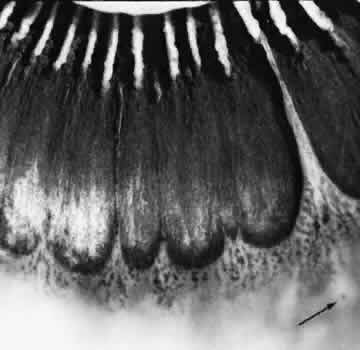

TYPICAL CYSTOID DEGENERATION

The most common form of degeneration of the peripheral retina is typical cystoid degeneration. Spaces develop in the outer plexiform and inner nuclear layers and coalesce to form interlacing tunnels; they are separated by pillars that extend from the inner to the outer retinal layers, giving the inner surface a uniformly stippled appearance (Fig. 15). The stippled depressions correspond to retinal pillars; the intervening rounded domes result from the intraretinal cystoid spaces.9 Degeneration begins at the ora serrata, particularly at the base of dentate processes, and extends posteriorly and circumferentially to form a band that may encircle the eye and reach from the ora serrata to the equator (Fig. 16).

Fig. 16. Typical and reticular cystoid degeneration found immediately behind the ora serrata and about enclosed ora bay near cut edge of calotte. Posteriorly, note the conspicuous vascular pattern of degeneration (seen as gray background), finely stippled surface pattern, and angular free margins (related to limitation by surface vessels).

This degenerative process may be noted in infants at 1 year of age; it is always present in both eyes of patients over 8 years of age, usually increases in area with advancing age, and is most extensive in the superior and temporal quadrants (see Table 3).10,11